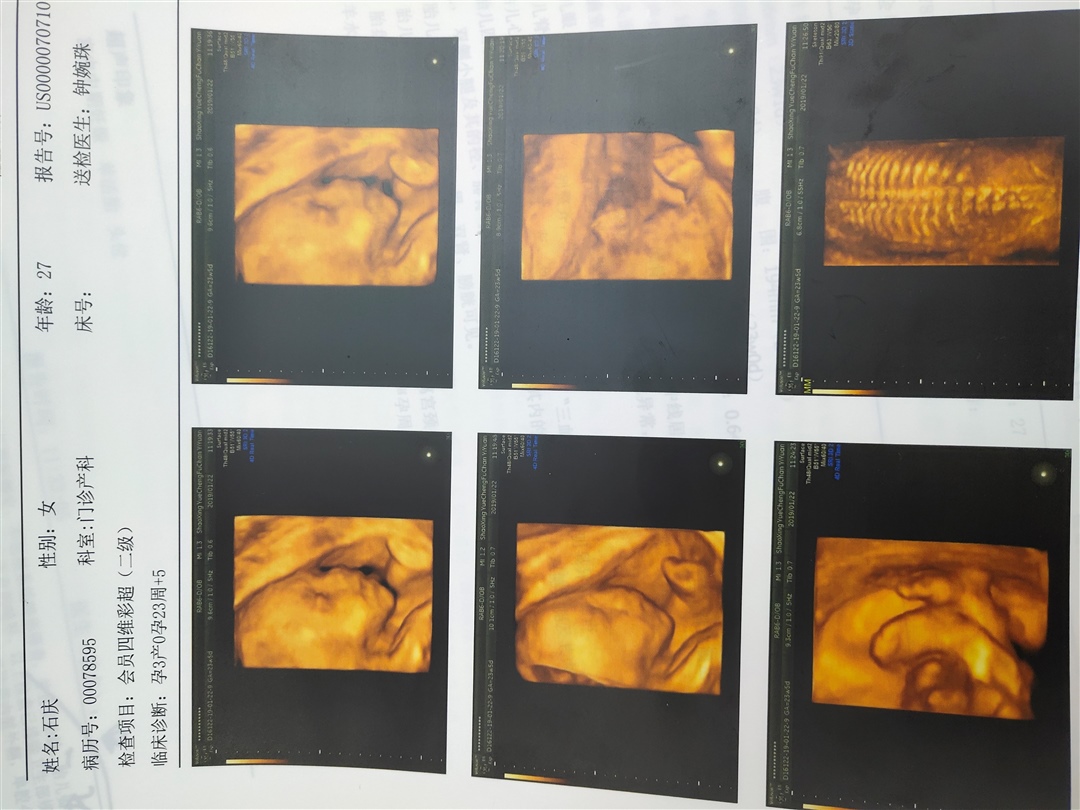

四维做了多少钱啊?是公立医院做的吗?

简单🎈[帖主]:880

莹:好的,我这里都做不了四维。我只能约三维了

接四维一次顺利通过